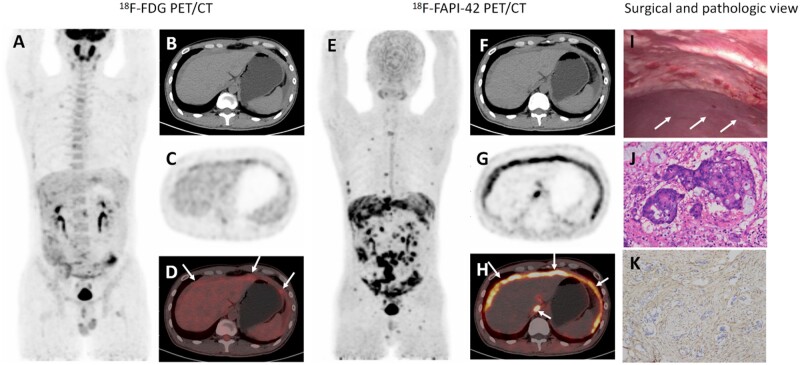

Background: Colorectal cancer is the third-most common type of cancer. When peritoneal metastasis (PM) develops, diagnosing metastatic lesions is difficult and the prognosis is poor. This study aimed to compare the value of fluorine-18 fibroblast activation protein-specific inhibitor (18F-FAPI-42) and fluorine-18 fluorodeoxyglucose (18F-FDG) positron emission tomography/computed tomography (PET/CT) for detecting PM of colorectal cancer and to guide clinical decision-making.

Methods: Forty-eight patients with PM who underwent both 18F-FAPI-42 and 18F-FDG PET/CT examinations were studied. The maximum standardized uptake value (SUV max), tumor-to-background ratios (TBRs) and peritoneal cancer index (PCI) of the PM were compared between the two imaging techniques. The intraclass correlation coefficient (ICC) was used to compare the consistency between the PET/CT PCI score and the intraoperative PCI. A receiver-operating characteristic curve was used to predict the accuracy of CC-0 cytoreduction (complete cytoreduction with no visible disease).

Results: The sensitivity and accuracy of 18F-FAPI-42 PET/CT for detecting PM were higher than those of 18F-FDG PET/CT (82.1% vs 61.1%, P <0.01; 84.6% vs 74.5%, P <0.01). The median SUV max and TBR of PM was greater in 18F-FAPI-42 than in 18F-FDG PET/CT [4.8 (1.9-20.1) vs 4.7 (1.0-11.0), P =0.02; 4.3 (1.4-14.6) vs 2.9 (0.6-8.0), P <0.01, respectively]. The median PCI of PM based on 18F-FAPI-42 PET/CT was greater than that based on 18F-FDG PET/CT (15 vs 9, P <0.01). The ICC for 18F-FAPI-42 PCI was greater than that for 18F-FDG PCI (0.915 vs 0.724, P <0.01). The cut-off values of the PCI of the PM for 18F-FAPI-42 and 18F-FDG PET/CT to predict CC-0 were <18 and <10, with areas under the curve of 0.80 and 0.79, respectively.

Conclusions: 18F-FAPI-42 PET/CT has superior diagnostic efficacy for PM, particularly in the right upper epigastrium and small intestine. The PCI score of 18F-FAPI-42 PET/CT is very close to the intraoperative PCI score and has a high value for predicting CC-0. The individualized management of PM based on the 18F-FAPI-42 PET/CT PCI score is pivotal.